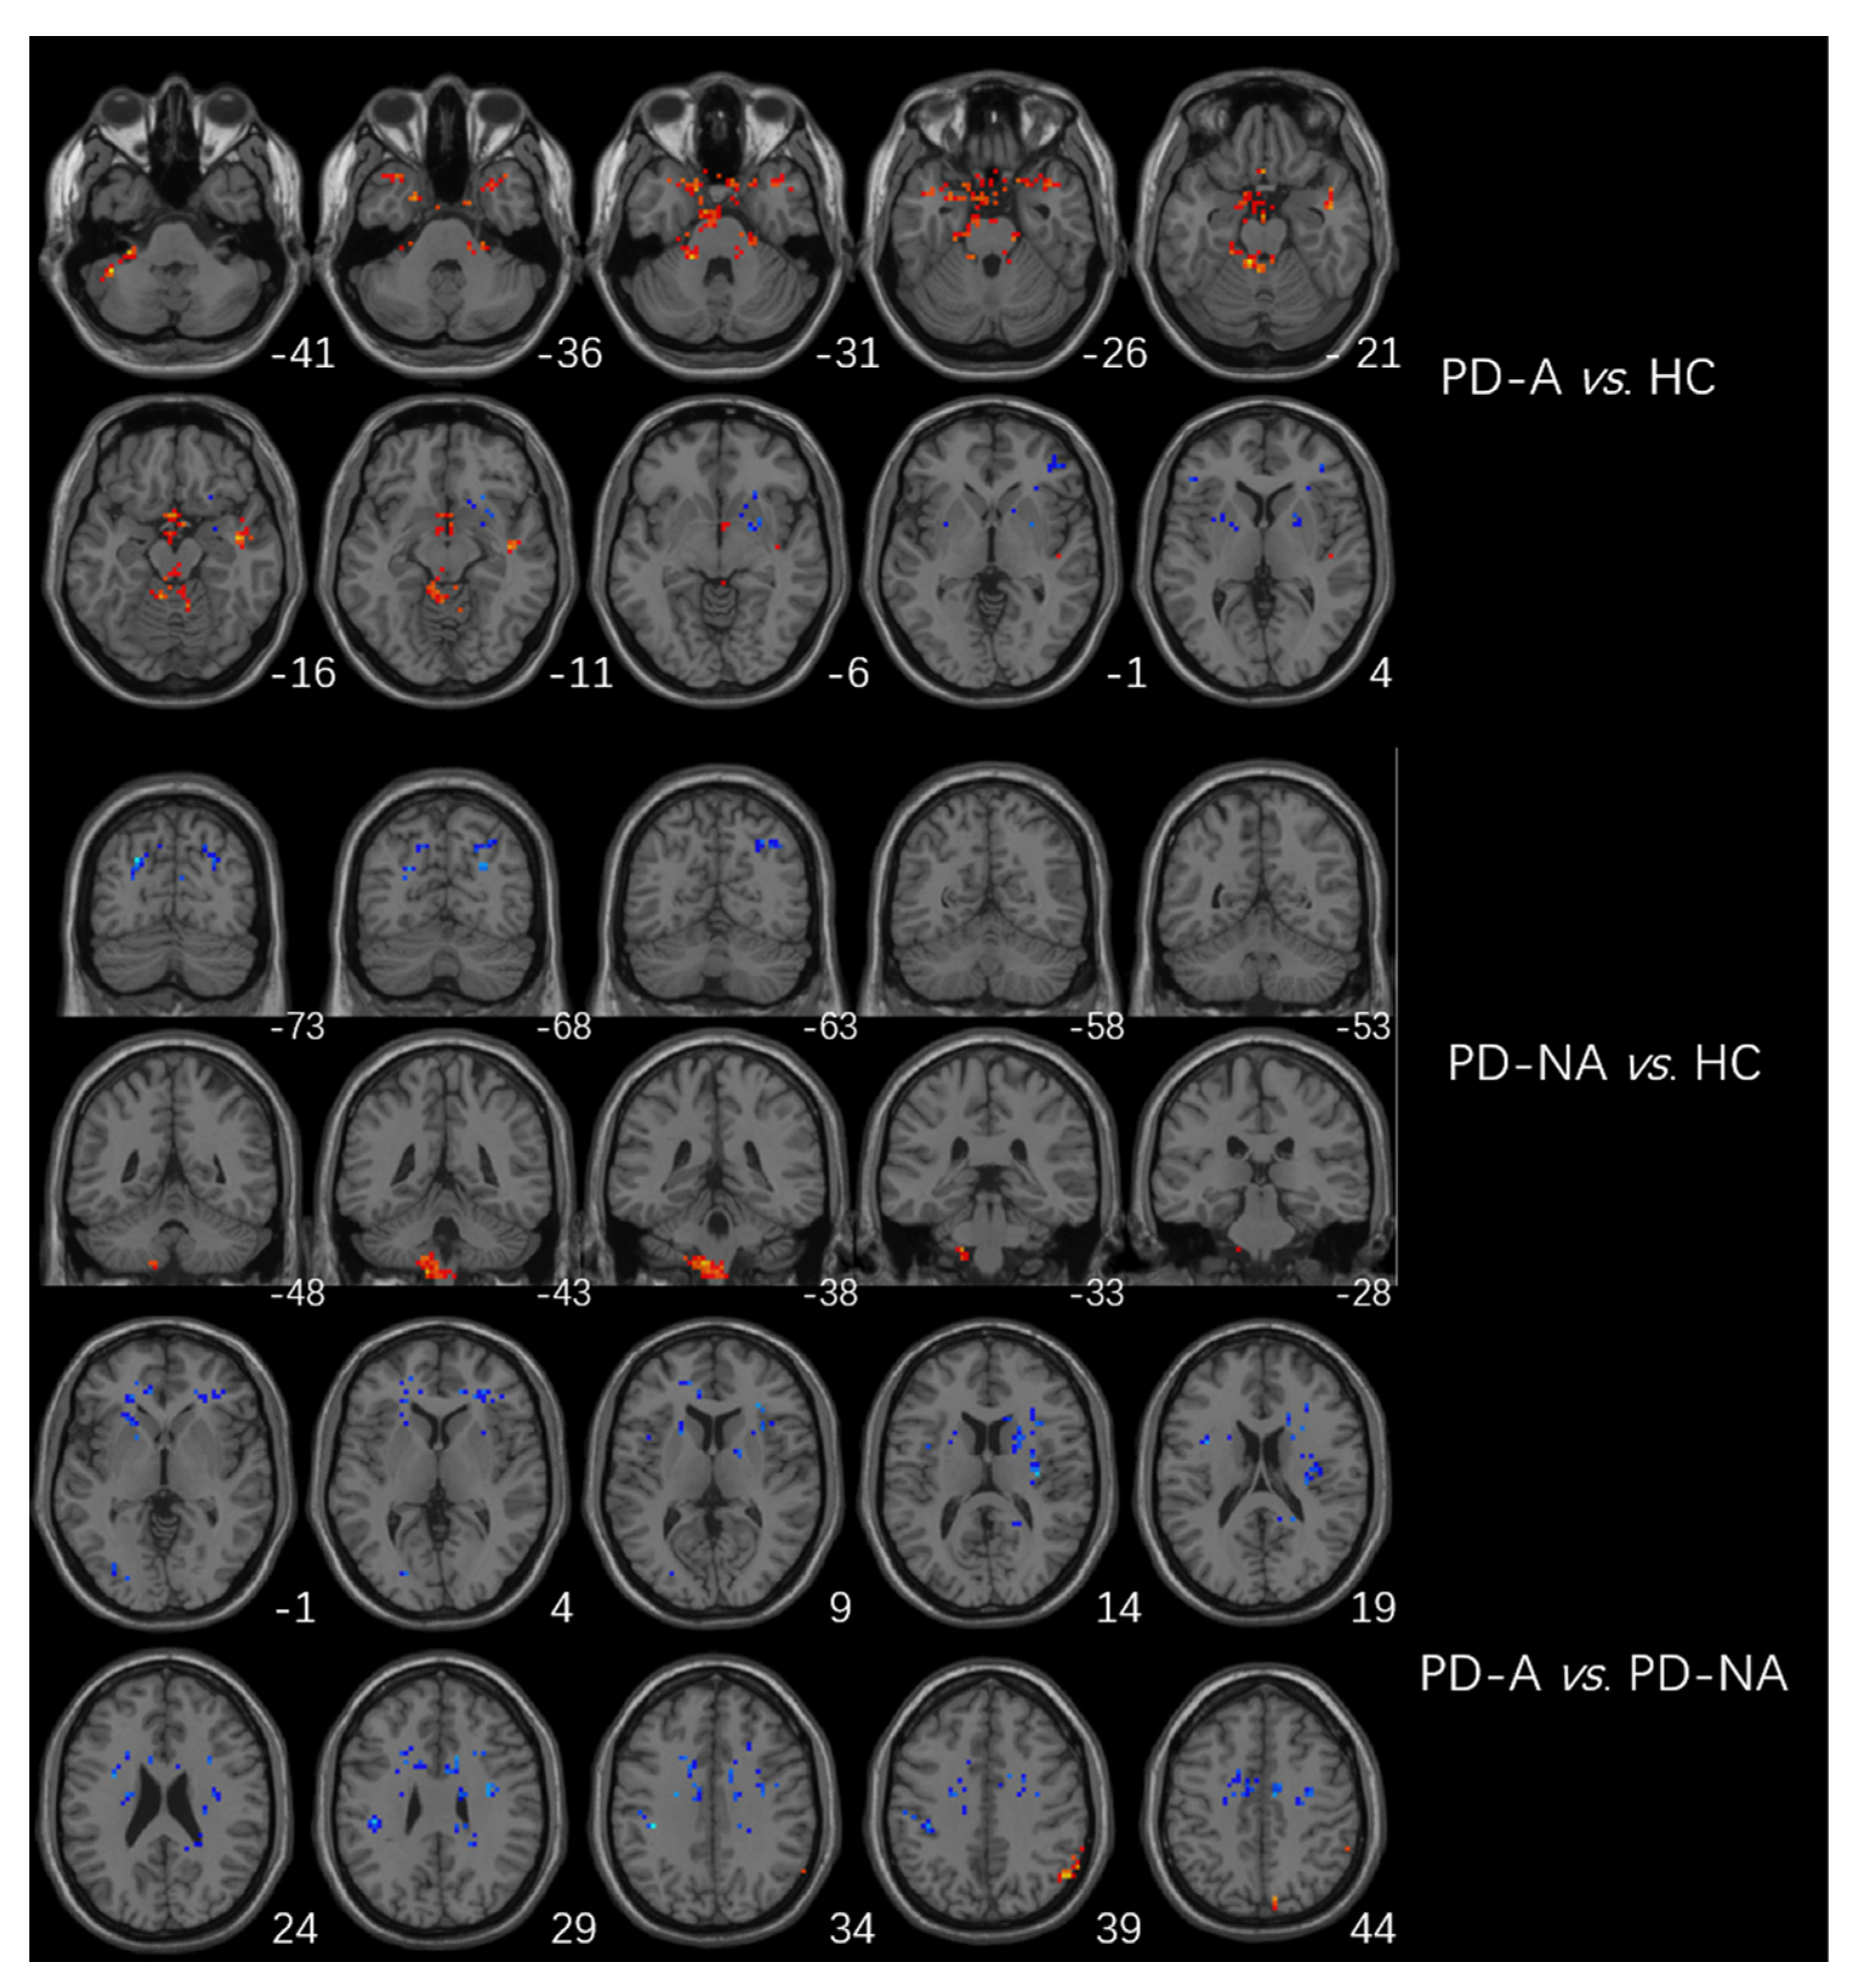

The higher fALFF values within the left cerebellum, posterior cerebellum lobe, bilateral temporal lobes, and brainstem, and the lower fALFF values within the bilateral frontal lobes, right basal ganglia areas, and left inferior parietal lobule were identified in PD-A patients compared with HCs (Table 3, Figure 2). Compared with HCs, PD-NA patients showed increased fALFF values in the left cerebellum and cerebellum posterior lobe. In contrast, decreased fALFF values were noted in the right cuneus and left superior parietal lobe (Table 3, Figure 2). When comparing the two PD groups, increased fALFF values of the right precuneus were found in PD-A patients. In contrast, decreased fALFF values were demonstrated in the bilateral frontal lobes, bilateral basal ganglia areas, left inferior parietal lobule, and left occipital lobe (Table 3, Figure 2). The fALFF values in the right precuneus (r = 0.54, p < 0.001) were positively correlated with HAMA scores of PD-A patients (Figure 3). Furthermore, the fALFF values in the left caudate were negatively correlated with HAMA scores of PD-A patients (r = −0.60, p < 0.001) according to Pearson’s correlation analysis (Figure 4).

Figure 2.

Brain regions showing differences in fALFF between groups. The red region represents the brain region with significantly increased fALFF (PD-A > HC, PD-A > PD-NA, and PD-NA > HC), and the blue region represents the brain region with significantly decreased DC (PD-A < HC, PD-A < PD-NA, and PD-NA < HC).